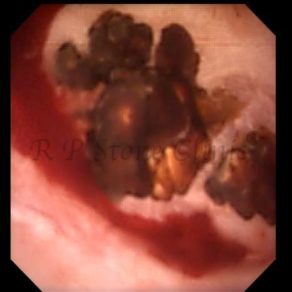

The Below Images Show Small Stones attached to the Renal Papillae.

Kidney stone is a solid mass of CRYSTALS. It is the process of crystallization which initiates the formation of kidney stones. This happens in nephrons or units of kidney. Once a small crystal is formed, it can both grow & unite with other crystals leading to the formation of small concretion which eventually forms a stone. Once these large crystals detach from the collecting ducts, the process of stone formation starts in the renal collecting system. A recurrent kidney stone former is advised to know a little bit about something known as Randall’s plaque. Alexander Randall discovered plaques on the renal papillae eight decades back based on examination of 1154 pairs of autopsied Kidneys. He described these renal papillary lesions as cream colored or milk patch areas composed of calcium phosphate & calcium carbonate. These plaques could act as NIDUS for formation of KIDNEY STONE. Calcium Oxalate stone can form on this nidus & then detaches from this plaque to become a free floating stone in the collecting system of kidney

These images are taken as snap shots from the video recording of RIRS Surgery done at our hospital. These are Randall’s Plaques seen with Digital FLEX XC & Digital FLEX XC S. The cream or whitish patches are seen on the tips of RENAL PAPILLAE as seen in images below.